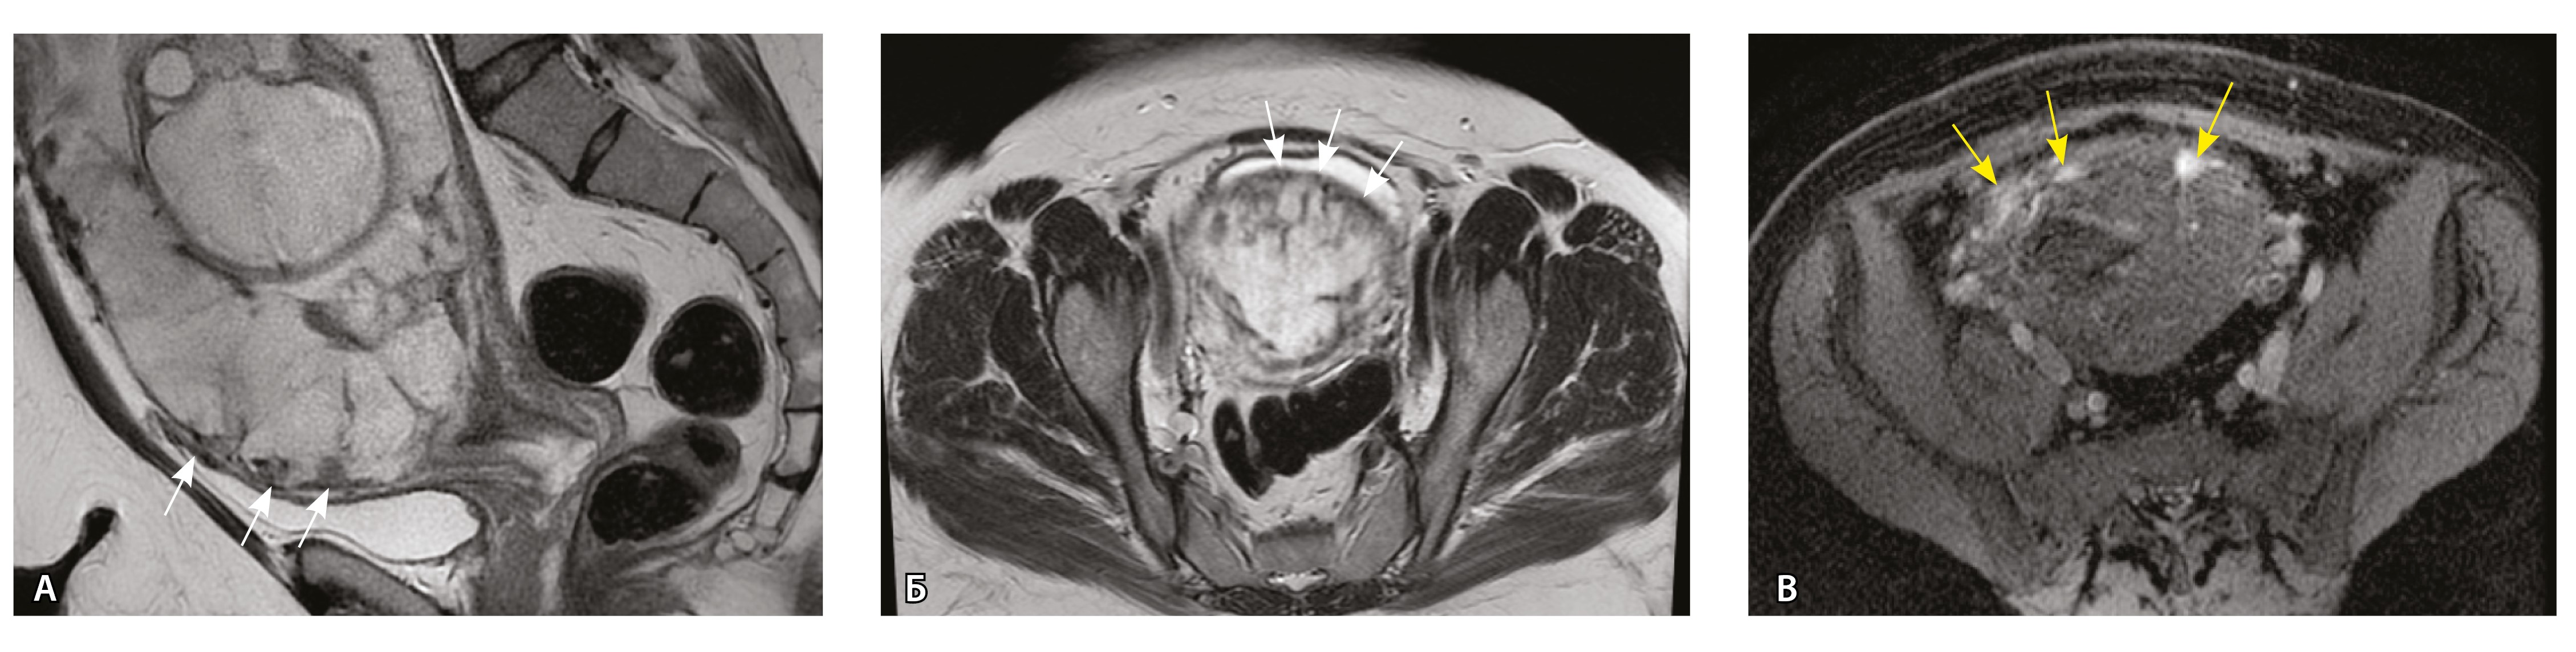

Сосуды 2-го типа. Единичные сливающиеся сосудистые полости в маточно-плацентарной области, мелкие ретроплацентарные гематомы, участки с белковым содержимым по МР-сигналу в зоне контакта ворсин со стенкой матки (рис. 4).

Рис. 4. Беременность 32 недели, pl. accreta, PAS 1 по FIGO. На магнитно-резонансных томограммах в режиме Т2-взвешенного изображения в сагиттальной (А) и аксиальной (Б) плоскостях видны сосуды на границе маточно-плацентарной области, сливающиеся между собой (белые стрелки), без выраженного дефицита толщины миометрия и рубца от кесарева сечения, без признаков выбухания стенки матки. На Т1-взвешенном изображении в режиме подавления сигнала от жировой ткани в аксиальной плоскости (В) выявляется наличие участков повышенного сигнала (желтые стрелки) на границе маточно-плацентарной области, что соответствует геморрагическому компоненту в подострой/хронической стадии (ретроплацентарные гематомы) либо белковому содержимому (фибриноид)

Непосредственное сравнение МР-картины с операционным материалом подтвердило, что полости с геморрагическим компонентом соответствовали ретрохориальным гематомам различной давности, чаще подострой и хронической стадий, которые состояли из гемолизированных эритроцитов, нитей фибрина сетчатого строения, а также замурованных атрофичных ворсин (рис. 5). Следовательно, констатация на МРТ фиксированных геморрагических полостей в маточно-плацентарной области отражает не гиперваскуляризацию стенки матки, а наличие ретрохориальных гематом в подострой/хронической стадии, что следует учитывать в клинической практике.